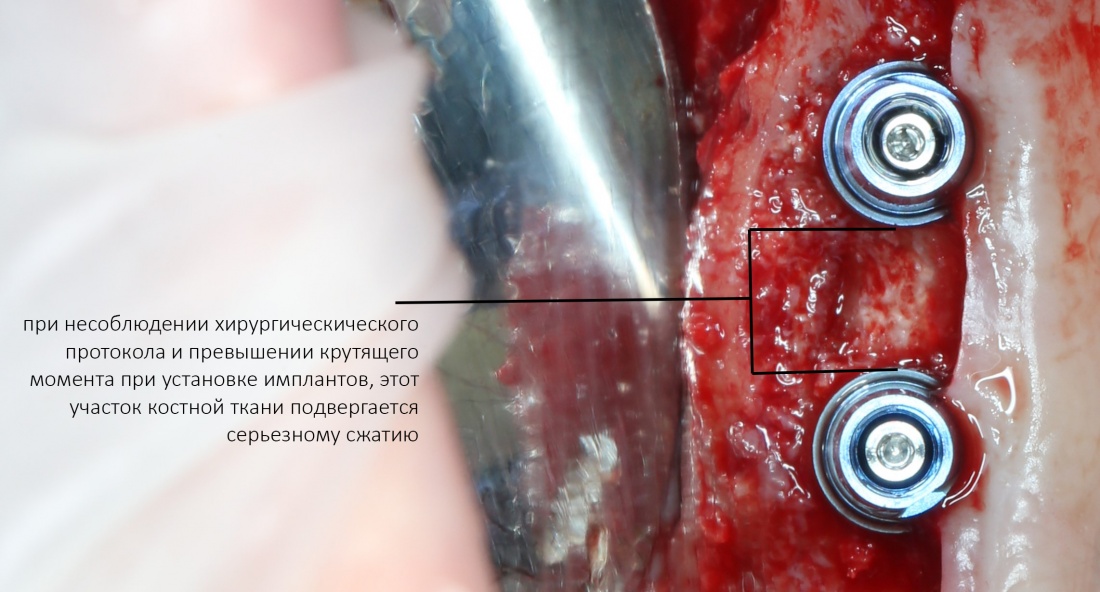

Однако, есть один нюанс, к которому любят апеллировать, если речь идет о позиционировании. Это расстояние между имплантатами, либо имплантами и естественными зубами.

Расстояние между имплантатами

Существует мнение, что между имплантатами, или имплантами и зубами должно быть выдержано определенное расстояние, по данным ряда авторов, от 1,5 до 3 мм, и это, как считается, необходимо для сохранения костной ткани. Типа, если между имплантатами останется совсем небольшой слой кости, то он потеряет питание, атрофируется — и превед, периимплантит. Этим мнимым правилом любят прикрываться, если речь идёт о неправильном позиционировании или неправильном подборе имплантов — дескать, «я выдерживал расстояние!». Или, что еще хуже, предлагают пациенту удалить, к примеру, нижние резцы по бокам от дефекта зубного ряда — типа, иначе не будет держаться…

Вместе с тем, существует масса примеров, когда костная ткань уходила, даже если имплантаты стояли на расстоянии 5 мм друг от друга:

или, наоборот, между имплантатом и зубом (либо имплантом и имплантом) оставалось расстояние менее миллиметра — и он они долго и счастливо служили, не имея проблем с уровнем костной ткани:

Как это можно объяснить?

Для начала, обратимся к расстоянию между естественными зубами и измерим межальвеолярные перегородки. Их ширина может быть значительно меньше миллиметра, но при этом они не атрофируются и не теряют высоту. Мы знаем, что сквозь корни зубов сосуды не растут — а это значит, что они как-то кровоснабжаются и при такой толщине верно? Следовательно, история о том, что «для кровоснабжения кости нужна какая-то определенная толщина» — не более, чем заблуждение:

Заменим зуб на имплантат. Что принципиально изменилось?

С точки зрения геометрии — ничего, как была перегородка, так она и осталась. Так почему же в некоторых случаях мы наблюдаем атрофию и потерю кости между имплантатами?

Не поверите, но проблема не столько в расстоянии, сколько в том, как мы готовим лунки под имплантат. В прорезывании зубов и «прорезывании» имплантатов есть принципиальное отличие — если первые не прорезываются мгновенно, и у костной ткани межкорневой перегородки есть время на построение и формирование микроциркуляторного русла, то при установке вторых мы мало того, что травмируем — мы зажимаем костную ткань между двумя несжимаемыми имплантатами, ишемизируя и без того плохо кровоснабжающийся участок:

и получаем закономерный результат — всё, что остаётся без питания, обижается и ,рано или поздно, уходит.

Какое решение? Его подсказывает сама ситуация:

- Готовим лунку, исходя из общих и вышеописанных правил позиционирования имплантатов.

- При подготовке лунки обращаем особое внимание на обработку кортикальной пластинки костной ткани. В данном случае, лучше сделать перепреп, чем недопреп.

- Устанавливая в лунку имплантат нужного размера в нужное положение, следим за торком (крутящим моментом). Он не должен превышать 20Нсм.

- Отныне забываем этот бред про расстояния между имплантами или имплантами и зубами, спокойно наслаждаемся работой.

Подводя итоги этого раздела, еще раз подчеркну, что имплантаты, один или несколько, должны быть установлены в позиции, максимально удобные для протезирования, а их размер позволял бы равномерно и без перекосов распределять жевательную нагрузку. Расстояние между имплантатами, либо между имплантом и зубом, может быть любым при условии, что лунки подготовлены правильно, а крутящий момент при установке имплантов не превышал 20 Нсм.